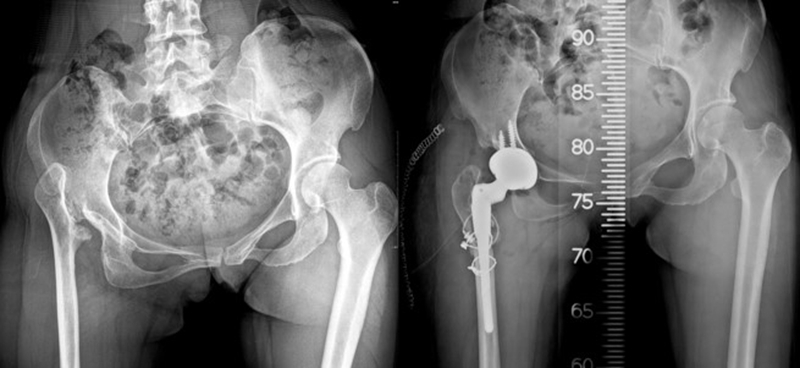

干骺端畸形还可引起髓腔增宽,骨量减少,骨质疏松,不能为近端压配固定型的假体提供良好稳定。宜选用全微孔涂层远端固定假体。

(2)髓腔狭小

细长股骨柄与狭窄髓腔匹配。

(3)股骨成角畸形

程度轻,且远离假体安放位置:近端固定短柄假体或小号骨水泥型假体。

严重且靠近假体安放位置:必须行截骨矫正,以获得良好的对线。